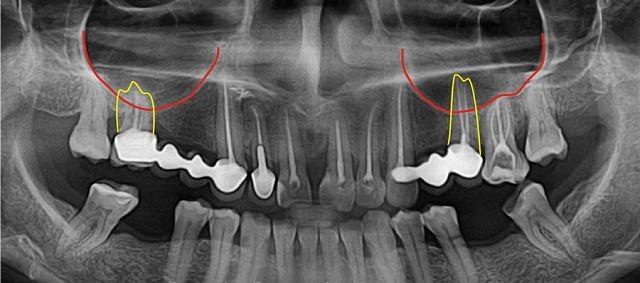

Для определения местоположения предмета необходимо провести рентгенографическое исследование. Также рекомендуется пройти компьютерную томографию и другие методы, которые помогут точно установить местонахождение объекта.

| Диагностика | Рентген, КТ (компьютерная томография) пазух носа, эндоскопическое исследование. | Выявление инородного тела в пазухе, оценка степени воспаления и повреждения тканей. |

Согласно статистическим данным, более 40% случаев попадания инородных объектов в гайморовую пазуху связано с некачественным лечением зубов. Поскольку верхний ряд зубов располагается очень близко к гайморовой пазухе, при проведении пломбирования может произойти перфорация верхней челюсти.

В результате этого пломбировочный материал может легко попасть в указанную область. Из-за естественной тонкости стенок верхней части рта, инородный предмет без особых трудностей проникает в гайморовую пазуху.

- Рентгенография: Один из первых методов визуализации, который позволяет выявить наличие инородного тела. Рентгеновские снимки могут показать тени, которые указывают на присутствие пломбировочного материала, особенно если он содержит металлы.

- Компьютерная томография (КТ): Этот метод является более информативным и позволяет получить детализированные изображения гайморовых пазух. КТ помогает точно определить местоположение инородного тела, его размер и возможные осложнения, такие как воспаление или инфекция.